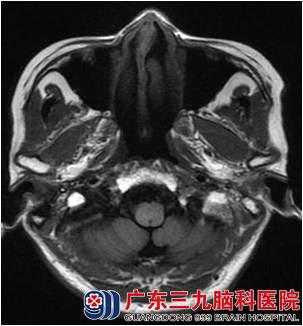

龚小姐于2012年9月因“右颈肿物3年余”,外院活检病理示:鼻咽未分化型非角化性癌。查体:右颈II区淋巴结约26mm X 15mm,边界尚清。9月12日胸部DR未见异常未见骨转移及身体其他部位转移征象,为进一步治疗,于10月份和11月份来广东三九脑科医院肿瘤综合治疗中心行鼻咽癌适形调强放疗,放疗50Gy/25f后复查鼻咽MR示鼻咽病变及颈部淋巴结影基本消失。7000cgy/35f,双颈部放疗5000cgy/25f,右上颈部推量至6000cgy/30f,放疗顺利放疗后行4周期低毒性化疗。

治疗过程很顺利,目前治疗后近2年,复查鼻咽MR:1.鼻咽癌放疗后改变,目前鼻咽部未见明确肿瘤复发征象;2.原右侧颈部颈动脉鞘旁稍大淋巴结已消失。